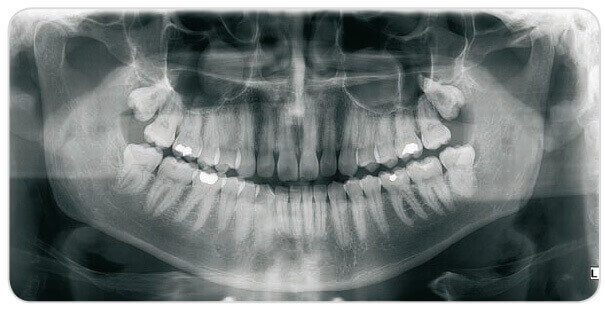

The process for digital dental radiology is similar to traditional dental X-rays that use film only in the fact that our dentist inserts a sensor into your mouth to capture images of your teeth. Although this sensor resembles the film used for bitewings and other X-rays, the digital sensor is electronic and connected to a computer. Once the X-ray is taken, the image is uploaded to a computer where our dentist can use imaging software to view the images in greater detail.

Higher Quality Image – The standard size of traditional X-rays can make viewing difficult, but digital X-rays can be enlarged or magnified for a better visual of the tooth’s structure. Brightness, contrast and color can also be adjusted, allowing your dentist to diagnose the proper treatment needed.